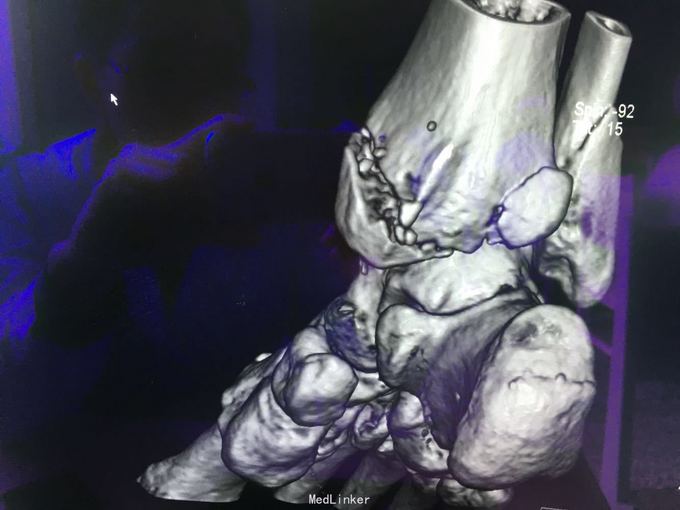

查体:左肾区叩痛,无皮肤隆起,未扪及肿块;腰椎压痛,活动受限,双下肢感觉存在,右小腿石膏托外固定,有踝关节明显肿胀,局部压痛活动受限,指端感觉血运可。 CT及X片:L2、L4椎体爆裂性骨折,L1-L4左侧横突骨折,右坐骨支骨折,右侧胫骨内、后及右侧腓骨外踝骨折,右足第1-4跖骨向外侧脱位及半脱位,伴近端斯脱性骨折。左肾挫裂伤,左肾重度积水,左肾周血肿。

诊断:右足lisfrance损伤,左肾挫裂伤;左肾周血肿,左侧输尿管结石伴左肾重度积水,L2、L4椎体骨折,L1-L4左侧横突骨折,右侧坐骨支骨折,右三踝骨折,全身多处皮肤软组织挫伤 处理:急诊行左肾探查,左肾切除术,择期行经后路腰2、4椎体骨折切开复位、椎公根螺钉内固定术+右内、外踝骨折切开复位内固定术,择期行右足lisfrance关节复位克氏针内固定术。